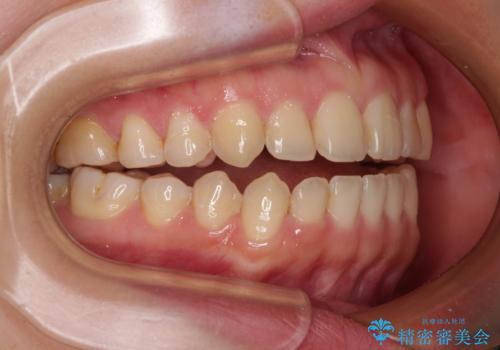

- 1年6ヶ月

- 5-10回

- 90万円(税込)費用は治療当時の料金となります